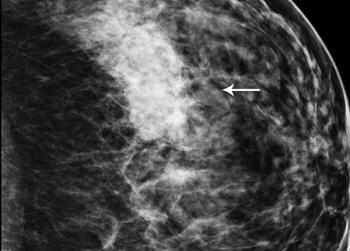

49-year-old patient presented for bilateral screening mammogram as well as bilateral screening ultrasound due to dense breast tissue.